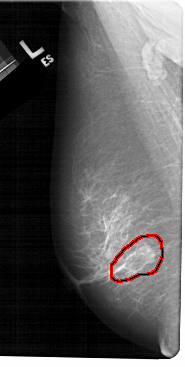

FILE: A_1243_1.LEFT_CC.OVERLAY

TOTAL_ABNORMALITIES 1

ABNORMALITY 1

LESION_TYPE CALCIFICATION TYPE FINE_LINEAR_BRANCHING DISTRIBUTION LINEAR

LESION_TYPE MASS SHAPE OVAL MARGINS ILL_DEFINED

ASSESSMENT 5

SUBTLETY 4

PATHOLOGY MALIGNANT

TOTAL_OUTLINES 1

BOUNDARY